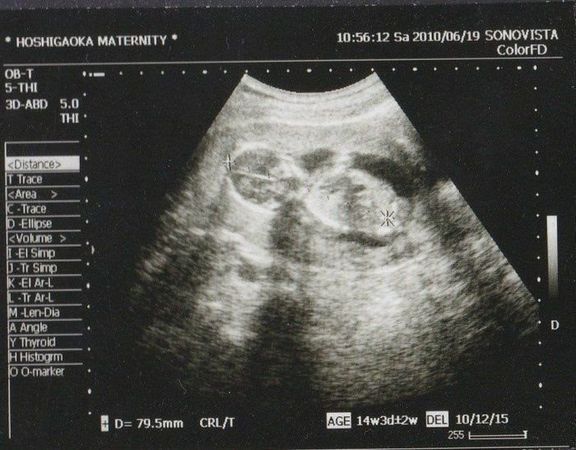

命の始まりは神秘的!2D・3D・4Dのエコー写真で見る「私と赤ちゃんの実録260日」 -

直前でまさかの性転換?みんなの予想を裏切り、ある日突然男の子になった我が子 -

エコー写真とともに綴る、愛しい我が子との“絆”を実感した妊娠期~ママと娘の265日~ -

エコー写真とともに綴る、愛しい我が子との“絆”を実感した妊娠期~ママと娘の265日~ -

緊急帝王切開で誕生。エコー写真で綴る息子と過ごした252日 -

緊急帝王切開で誕生。エコー写真で綴る息子と過ごした252日 -

不妊治療や2度の流産経験を経て「初めての出産」。日々成長する胎児の記録をエコー画像で振り返る -

待望の妊娠判明!エコー写真に見る、我が子を胸に抱くまでの“命の軌跡275日” -

エコー画像で振り返る、私に宿った小さな命が大きく育って誕生するまでの記録 -

推定体重は3773g!骨盤に入らず緊急帝王切開になった長女の成長をエコー写真で振り返る -

生まれる前からエコーを通して対面し、長女を少しずつお姉ちゃんにしてくれた次女の存在 -

生まれる前からエコーを通して対面し、長女を少しずつお姉ちゃんにしてくれた次女の存在